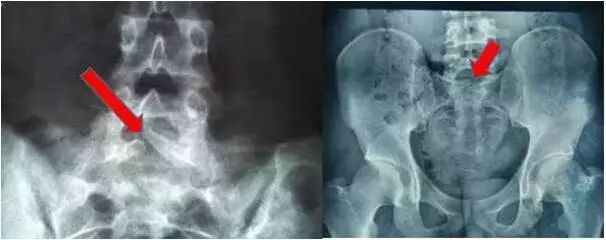

门诊经常遇到因为腰痛来就诊的患者,经拍片、CT检查,除骶椎隐裂外,再无其他阳性发现。有的患者是因为车祸或外伤后腰痛就诊,经拍片检查没有发现骨折,也同样是发现了骶椎隐裂。向患者交待病情时,患者一般惊诧和迷茫:骶椎隐裂?先天的?确定不是外伤造成的?能治好吗?以后不会瘫吧?一连串的问题,让人不知从何答起。 正常情况下腰椎或骶椎后方棘突是连在一起的,脊椎的发育就是一种骨化过程,直到青春期前,脊椎包括腰椎和骶椎仍未完全骨化,一般要在17-23岁方可完成。如果在停止发育之前没能未完全骨化成功,也就是在后方没有连成一个整体,在X光片上表现很像一道“裂痕”,因为在体外没有表现,一般是无意中发现,所以称为“隐性脊柱裂”,发生在骶椎就称为骶椎隐裂。 很多骶椎隐裂在一生中都不引起症状,只是在无意中发现。但隐裂较重者则因为局部构造较弱,易因劳损而产生慢性腰痛,骶裂伴游离棘突者在弯腰时棘突可刺激硬膜造成腰痛。当骶裂伴有L5棘突肥大时,伸腰时可刺激裂隙间的纤维膜或缺损椎板残端产生疼痛。当纤维膜与硬膜或神经产生粘连,则可引起下肢的放射痛。因此临床上有隐性脊椎裂且伴有明显坐骨神经痛者,应仔细分析隐裂的性质,分析其症状与体征特征,如有明显的神经根定位征,,移行椎在腰骶处表现为腰椎骶化或骶椎腰化,移行椎是发生腰背痛的原因之一。 诊断 脊柱X 线平片和CT 均能清晰显示椎管畸形,棘突及椎板缺损,明确诊断较为容易。 需要治疗吗?能治疗好吗? 骶椎隐裂,如果没有症状无需治疗。外伤一般不会造成这个部位骨折,也就是说外伤不会造成骶椎隐裂。如果有腰痛症状应避免久坐久站、长时间弯腰负重、剧烈运动或者外伤,腰部需注意局部保暖,并进行腰背肌功能锻炼以增强肌肉抗疲劳能力。当然如果病情较重已经严重影响患者正常的生活、工作则有可能需要手术治疗,而且需要专科医生进行专业地处理。